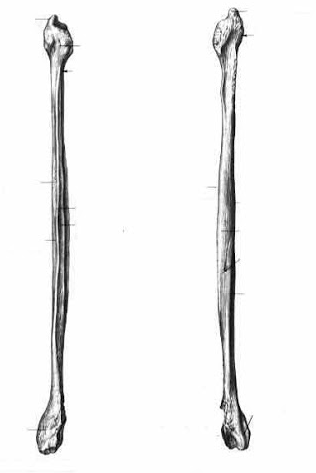

РОЗПІЗНАЙТЕ КІСТКУ. ПЕРЕЛОМ ЯКОЇ ЇЇ ЧАСТИНИ ВИ БАЧИТЕ НА РЕНТГЕНОГРАМІ?

варіанти відповідей

ULNA

RADIUS

FEMUR, ШИЙКА

ПРОКСИМАЛЬНОГО ЕПІФІЗА

ДИСТАЛЬНОГО ЕПІФІЗА

ДІАФІЗА

ЛІКТЬОВОГО ВІДРОСТКА

ПРОМЕНЕВОГО ВІДРОСТКА